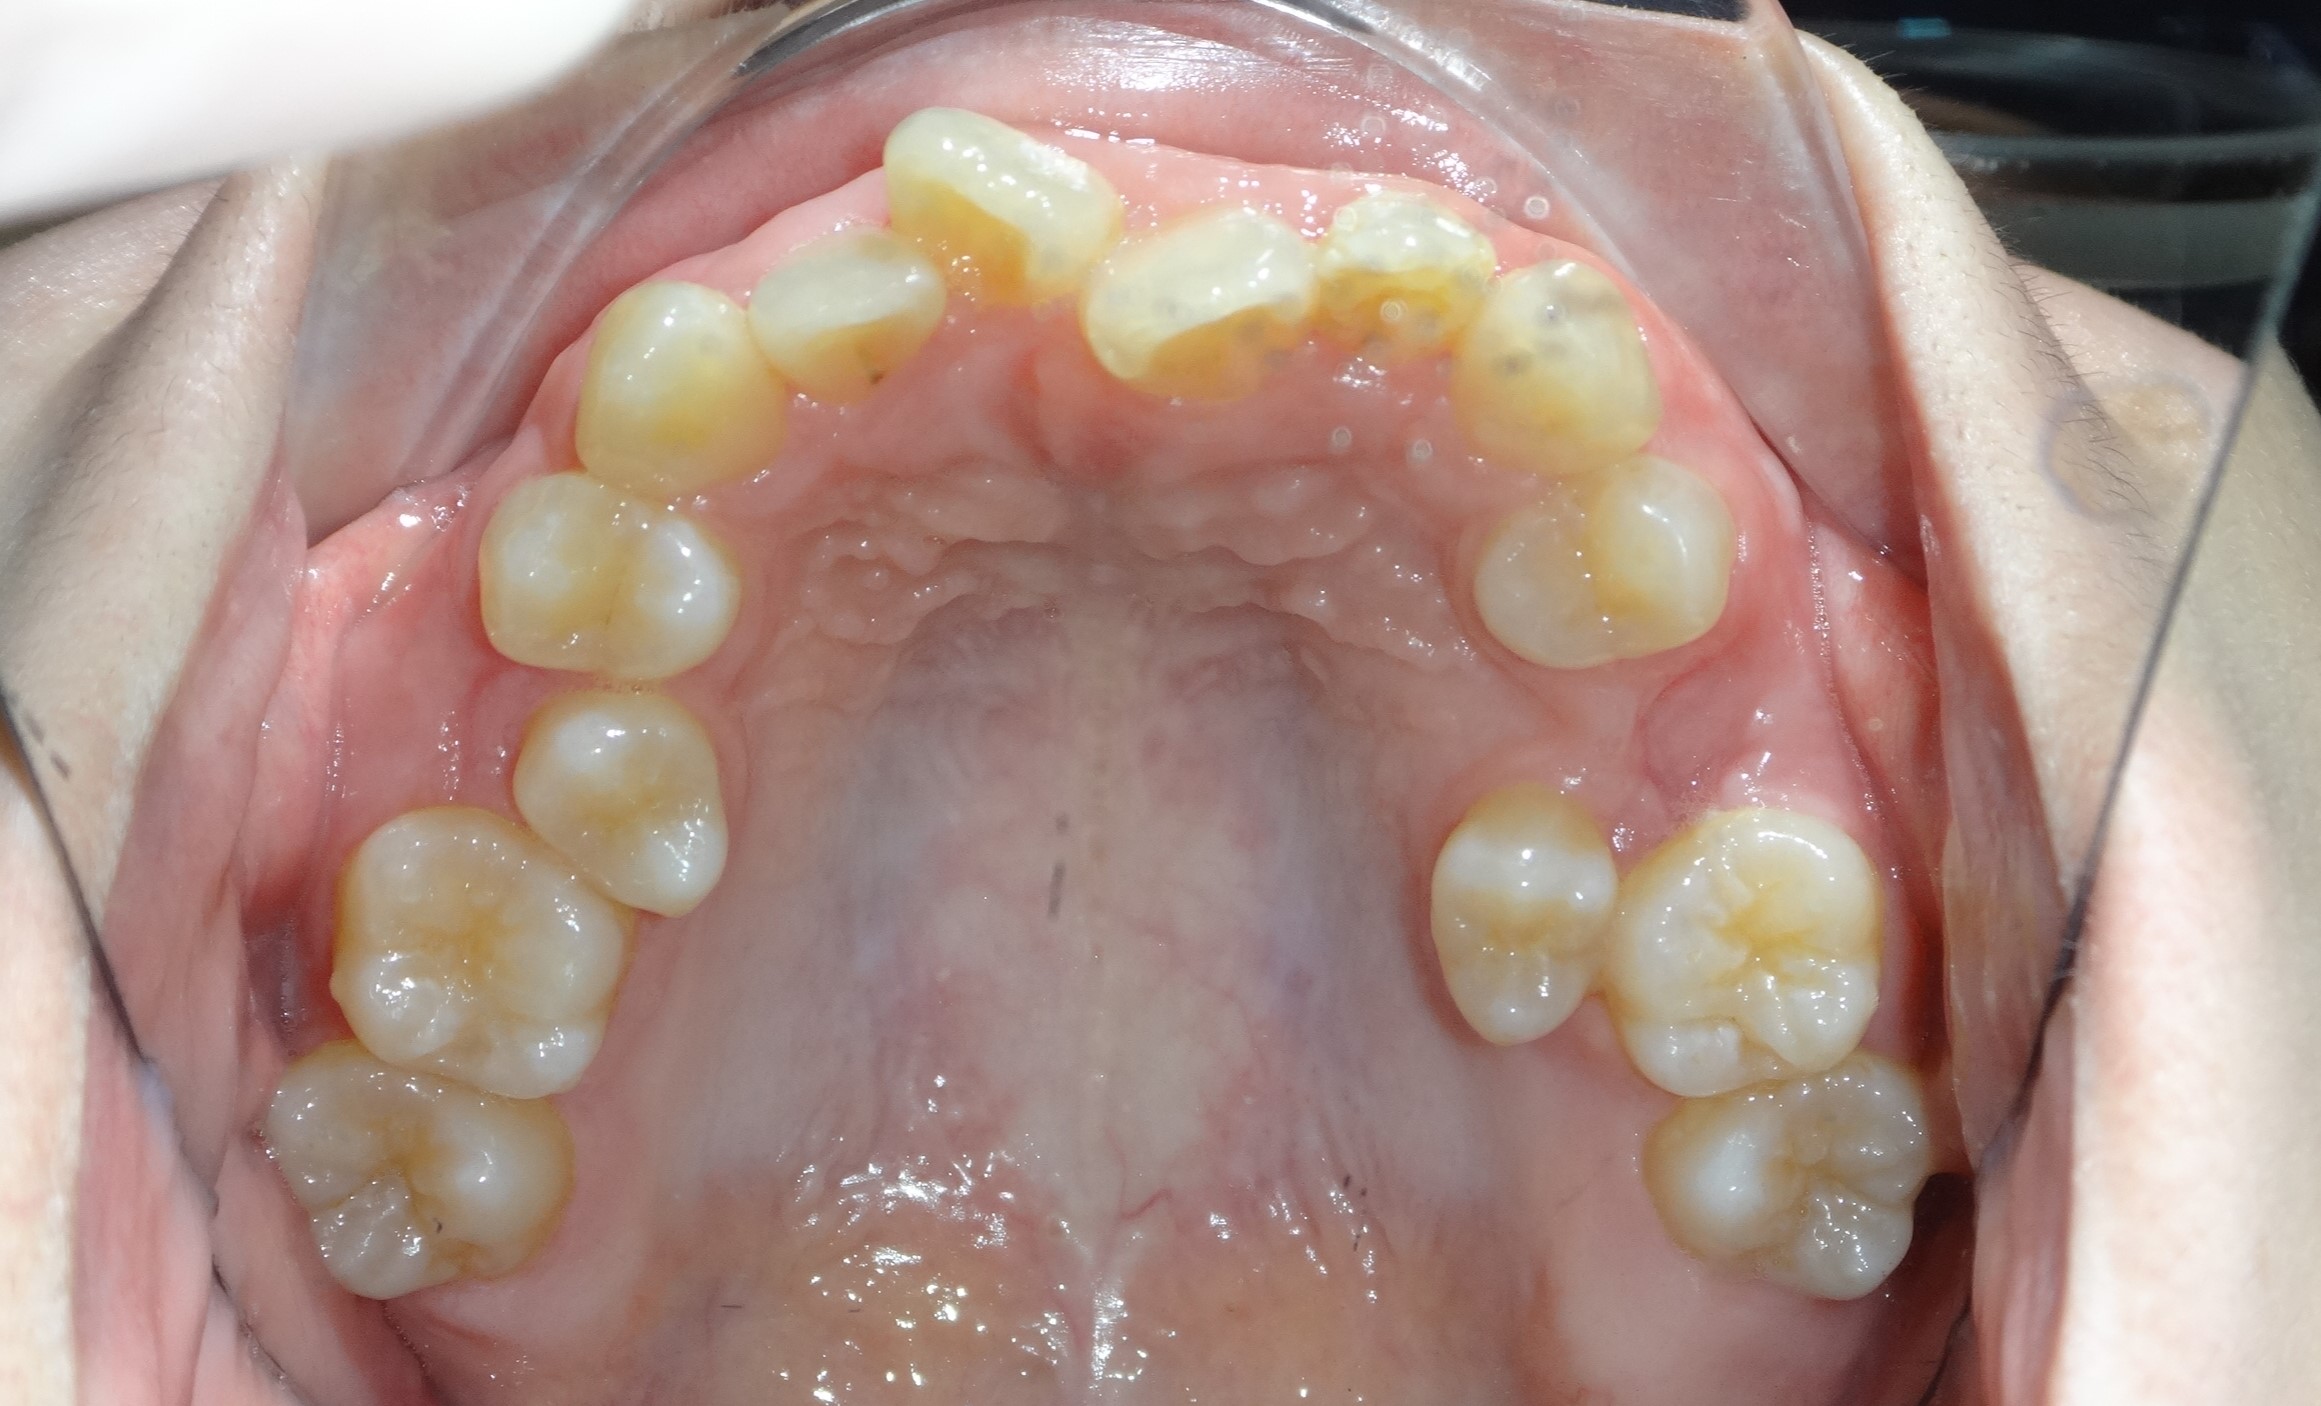

不拔牙案例 首頁 案例分享 齒顎矯正 不拔牙案例 - 矯正不拔牙案例 - 年紀:27歲 治療方式:隱適美隱形矯正 時間:34個月 主訴:前牙錯咬、排列不整 矯正前 矯正後 矯正前 矯正後 矯正前 矯正後 聲明:本所療程皆由專業醫生評估後,依照個人口腔狀況進行治療。因每位患者個別狀況不同,術後狀況也不盡相同,需親來本所由醫生評估。